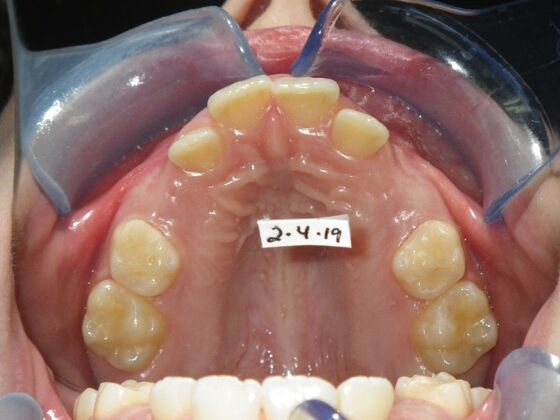

Patient presented with mixed dentition and mild deep overbite, excessive overjet,and rotated lower incisors. She also had a lower bilateral lingual retainer, preventing lower molars from coming forward. She was treated with utility archwires initially, waiting for eruption of cuspids and bicuspids. This was followed by conventional straight wire appliances and upper and lower standard hawley retainers.